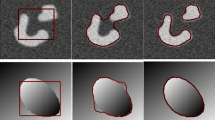

Due to the complex tissue structure of the breast, breast ultrasound (BUS) images exhibit the characteristics of low-contrast, lesion boundary blurring. Therefore, accurately automatic detection of ultrasound breast lesions is an important challenge for a computer-aided diagnosis system. Although previous saliency detection methods have been applied to detect breast lesions, they do not take full advantages of the prior knowledge of breast lesions. Here, to further accurately detect the breast lesions, a novel saliency detection method is proposed for BUS images, which seamlessly incorporates multiple priors into a hybrid architecture. To reduce the speckle noise and enhance the contrast, the BUS images are preprocessed by the methods of median filtering and a proposed adaptive thresholding. Also, to reveal the differences of benign and malignant lesions, a heat map based on the boundary of the breast lesions is established. Extensive experiments indicate that the proposed saliency detection method achieves an excellent performance of 0.925 accuracy, 0.871 sensitivity, 0.889 dice, and 0.912 F-measure on breast lesions detection in the BUS images, which is superior to the saliency detection models with a single prior. The boundary heat maps of the lesions also visually reflect the differences between benign and malignant lesions, which may potentially be used for automated computer diagnosis to assist radiologists in detection and identification of breast lesions.